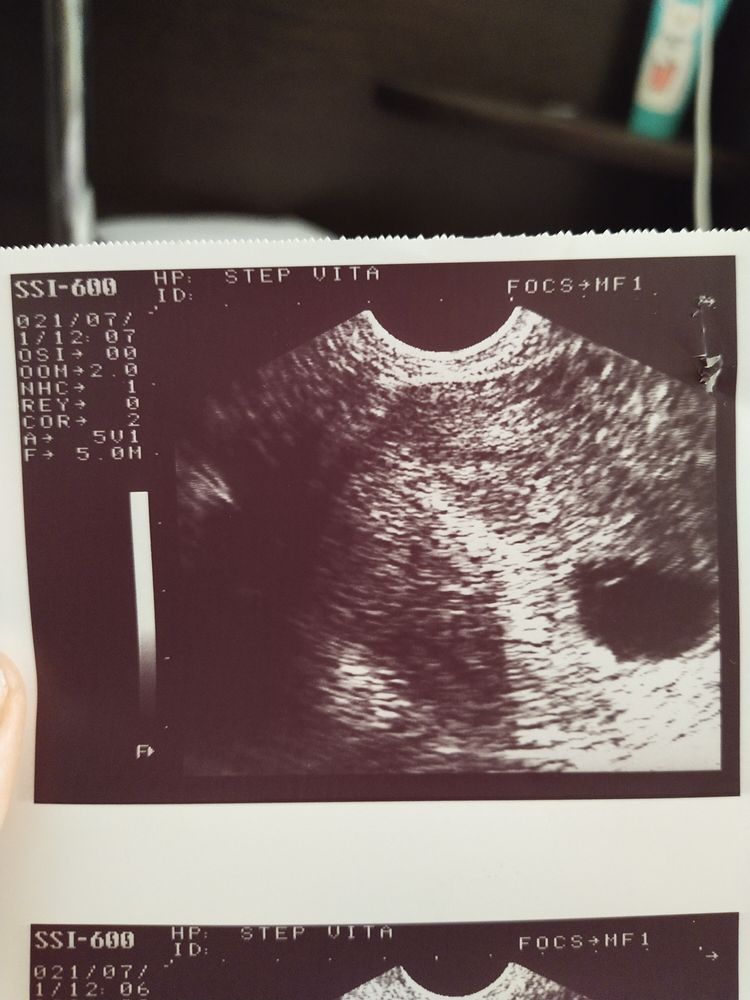

По месячным срок 5,1. Овуляция очень ранняя была. ПЯ 18мм, ЖМ 4 мм. Эмбриончик не визуализируется. Подожду ещё дней 10 и пойду у другому специалисту. Малыш я в тебя верю!